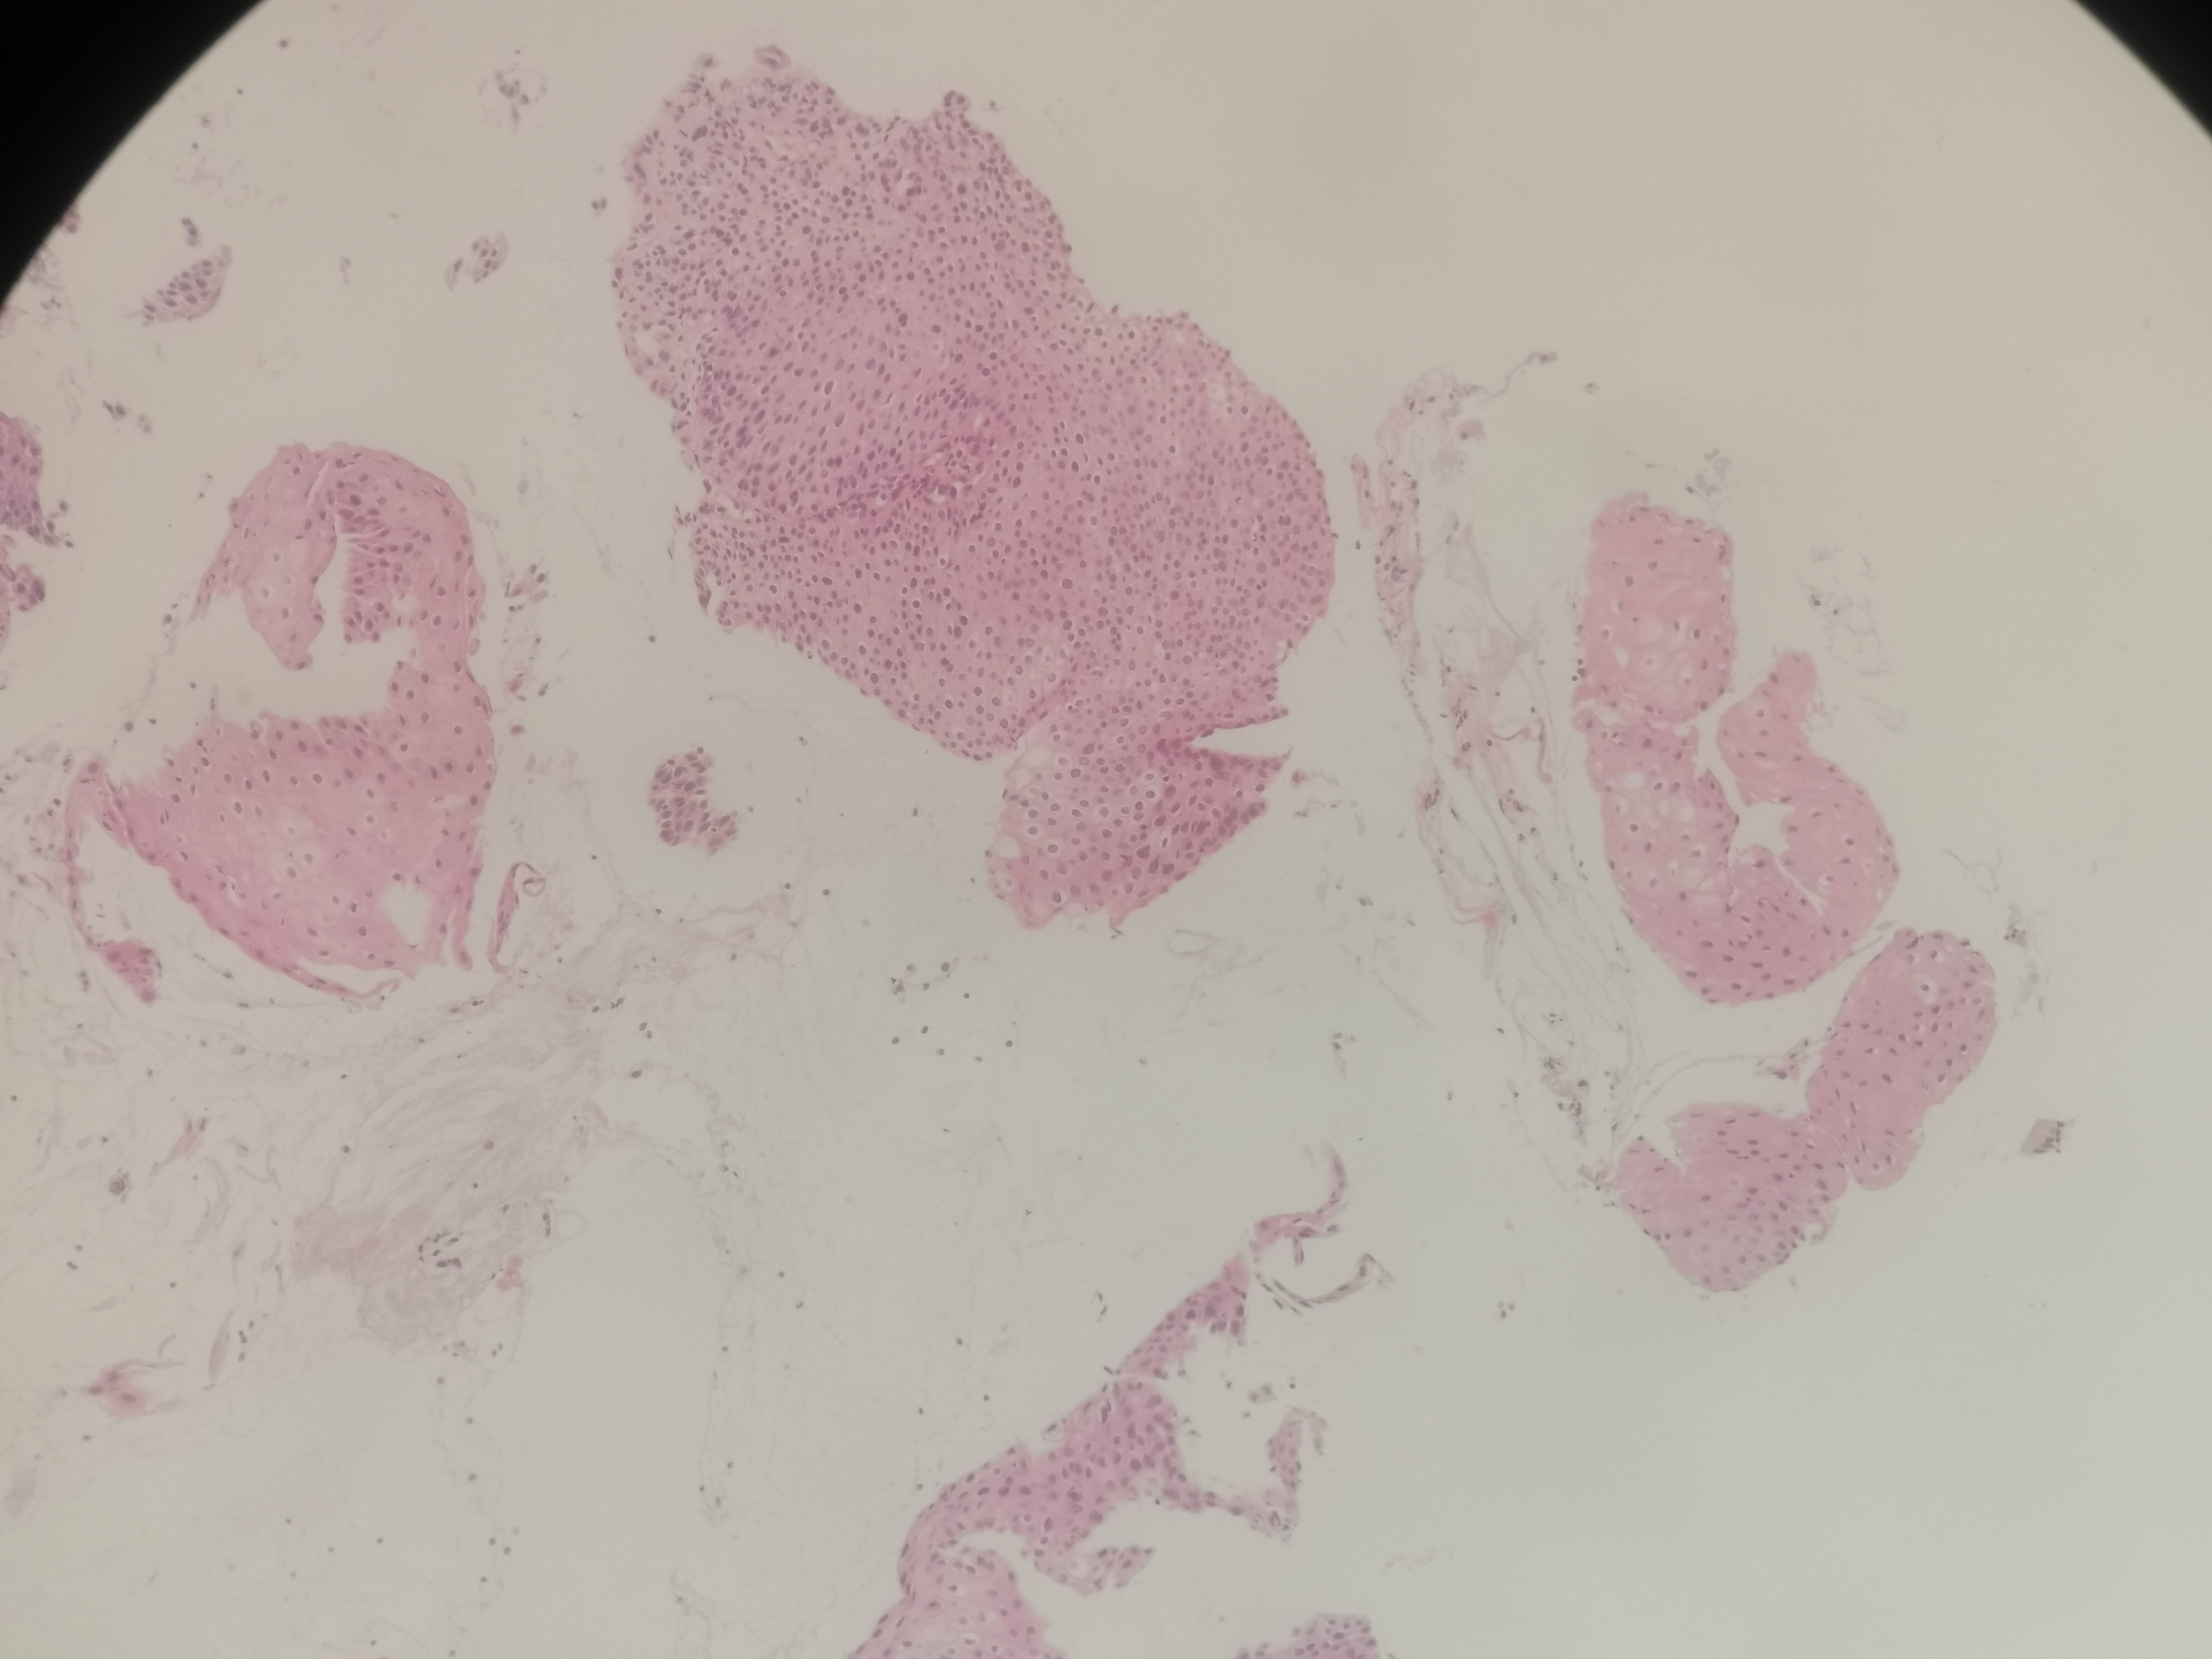

急!请老师帮忙看看,12点够CINii吗,还是报CINI~II

性别

女

年龄

59岁

临床诊断

HPV感染

一般病史

HPV16(+)

标本名称

宫颈活检组织

大体所见

3点:0.8x0.4x0.3厘米1块。6点0.7x0.6x0.3厘米1块。9点0.6x0.6x0.4厘米1块。12点0.8x0.5x0.3厘米,0.6x0.6x0.4厘米2块。

图1~16为12点2块组织,图17为9点组织,图18,为6点组织,图19为3点组织。

倾向低级别,标记看看